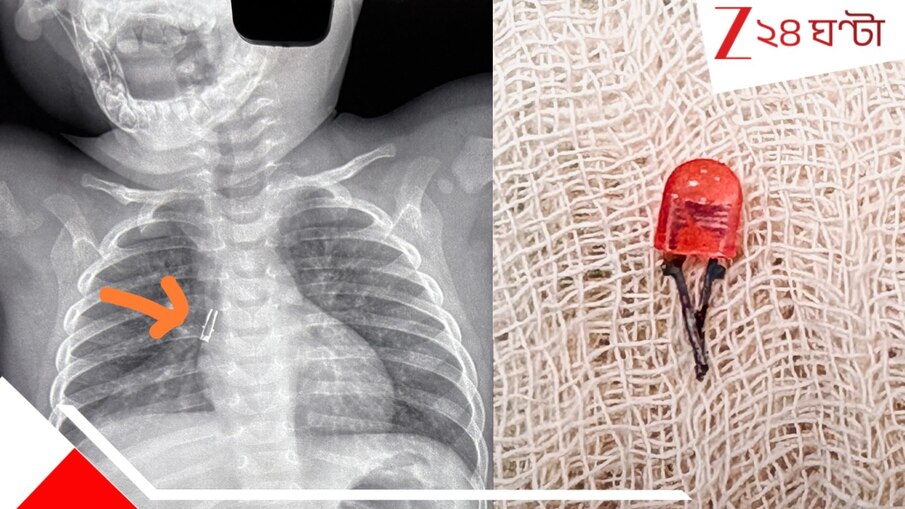

অয়ন শর্মা: মিরাক্যল করে দেখাল এনআরএস মেডিক্যাল কলেজ (NRS Medical College)। রিজিড ব্রঙ্কোস্কোপি (rigid bronchoscopy) করে ৮ মাসের এক শিশুর শ্বাসনালী (Respiratory Tube) থেকে খেলনার অংশ বের করে আনল এনআরএস মেডিক্যাল কলেজের বিশেষজ্ঞ দল (Saves 8 month old baby)।

শ্বাসকষ্ট ও কাশি নিয়ে শিশুটি ভর্তি হয়েছিল এনআরএস মেডিক্যাল কলেজ ও হাসপাতালে। ভর্তি হওয়ার পর প্রাথমিক এক্স-রে ও পরবর্তীতে এইচআরসিটি থোরাক্স-এ দেখা যায়, ডানদিকের মেইনস্টেম ব্রঙ্কস-এ আটকে রয়েছে খেলনার ভাঙা বাল্ব-জাতীয় একটি টুকরো। ডানদিকের লোয়ার লোব সম্পূর্ণভাবে বিধ্বস্ত হয়ে গিয়েছে। শেষে এই বিরল ও জটিল সমস্যার ক্ষেত্রে এনআরএস-এর বহুমুখী বিশেষজ্ঞ দল রিজিড ব্রঙ্কোস্কোপি করার সিদ্ধান্ত নেয়। বহুমুখী বিশেষজ্ঞ দলের সমন্বিত প্রচেষ্টায় মাত্র ৮ মাসের ওই শিশুর শ্বাসনালী থেকে খেলনার ভাঙা ক্ষুদ্র অংশ সফলভাবে বের করা সম্ভব হয়।

রোগীর অবস্থা স্থিতিশীল রাখার পাশাপাশি দ্রুত সিদ্ধান্ত নিয়ে জেনারেল অ্যানেস্থেশিয়া করে রিজিড ব্রঙ্কোস্কোপি-র মাধ্যমে আটকে থাকা ওই 'বিদেশি বস্তু'কে শনাক্ত ও অপসারণ করা হয়। সকলের মিলিত চেষ্টায় অত্যন্ত দক্ষতার সঙ্গে খেলনার ভাঙা বাল্ব-জাতীয় অংশটি বের করে আনা হয়। পুরো প্রক্রিয়াটি ছিল নির্বিঘ্ন। হাসপাতাল সূত্রে খর অপারেশনের পর শিশুটিও সম্পূর্রূপে হেমোডাইনামিক্যালি স্থিতিশীল আছে। প্রসঙ্গত শিশুদের শ্বাসনালীতে এভাবে কোনও কিছু আটকে যাওয়া চিকিৎসাবিজ্ঞানে জরুরি পরিস্থিতি হিসেবে বিবেচিত হয়। সেখানে একমাত্র দ্রুত সিদ্ধান্ত, যথাযথ ইমেজিং এবং অভিজ্ঞ হাতের ব্রঙ্কোস্কোপি-ই জীবন রক্ষা করতে পারে।